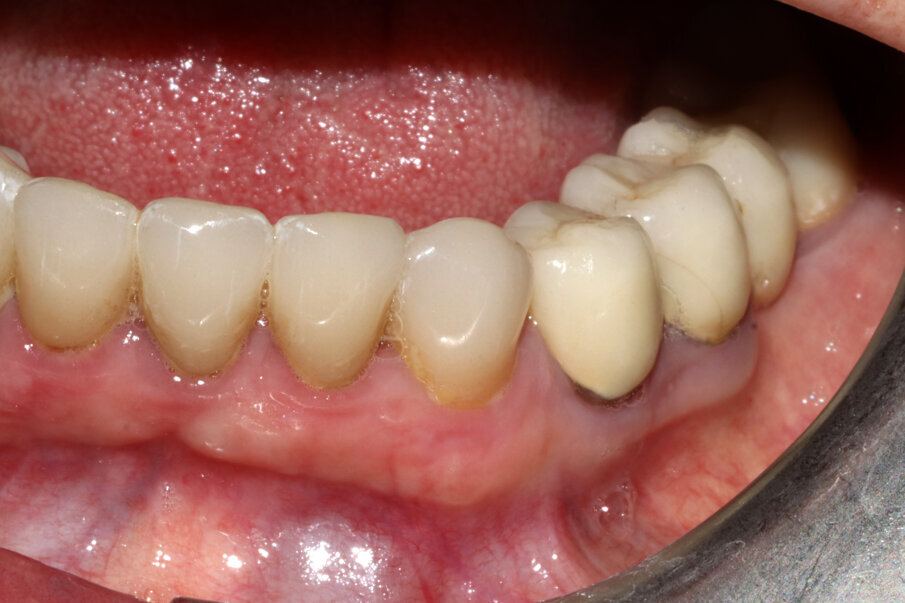

Il caso presentato riguarda una paziente di 62 anni, senza patologie degne di nota, già trattata presso altri studi professionali con una serie di riabilitazioni protesiche su monconi (corone singole). Nel 2021, si presenta alla nostra osservazione lamentando dolenzia costante sull’elemento 3.3 canino inferiore di sinistra, vitale e già rivestito con una corona in ceramica.

Fig. 3_Il caso clinico descritto: elemento 3.3 già rivestito di corona protesica, vitale e dolente.